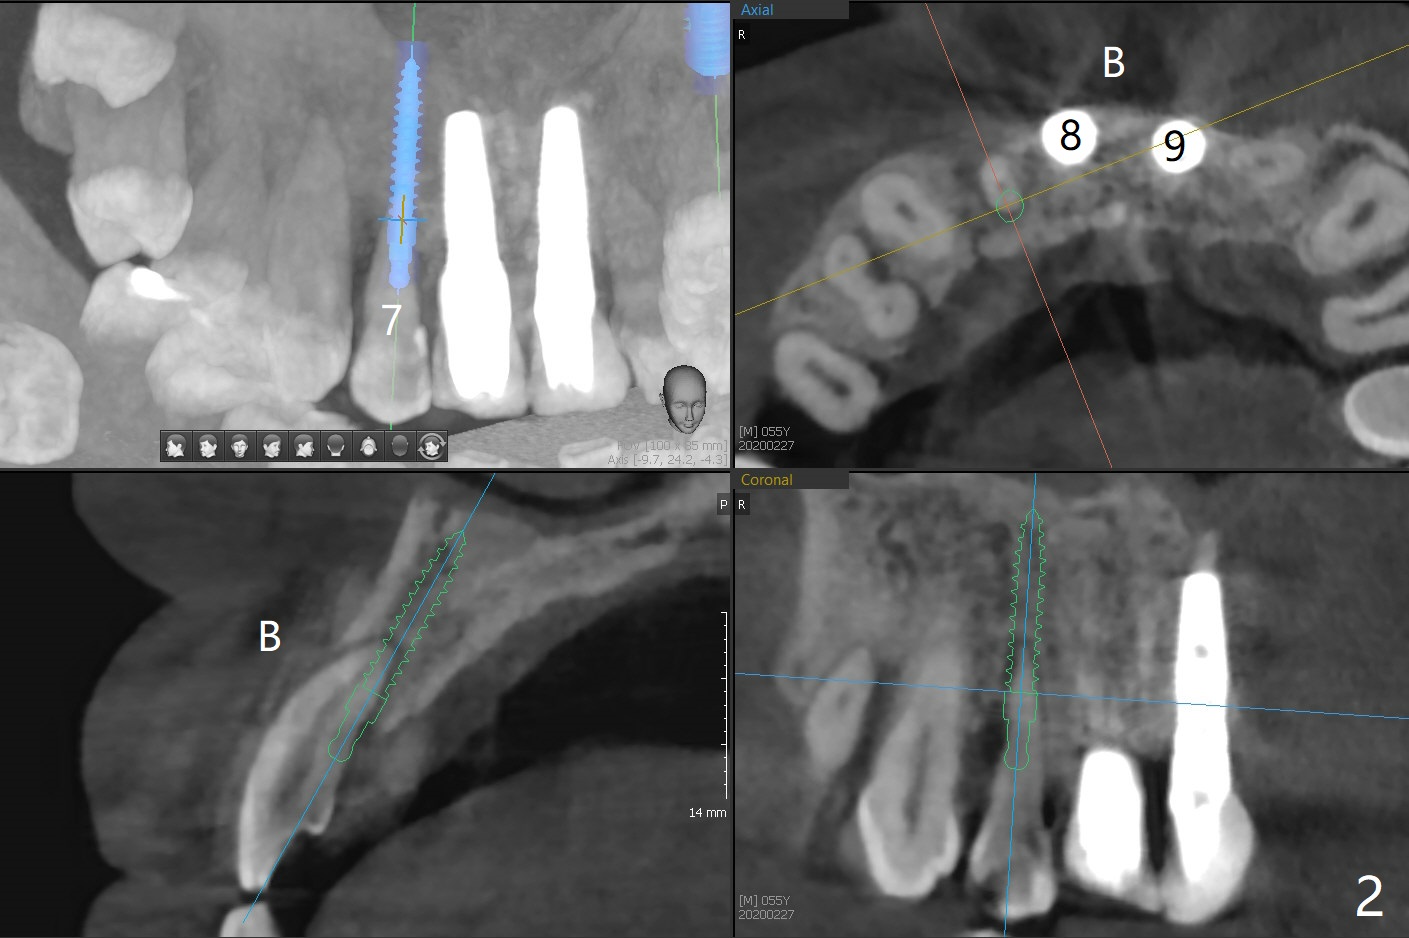

A 58-year-old man recently had sudden pain at #7 with labial plate loss (Fig.1 CT taken 3 years earlier). To avoid the labial placement of the large implants at #8, and 9, the implant at #7 will be smaller and palatally inserted (Fig.2). Fig.3 is a coronal section of 3D image of #7, showing the labial (B) and palatal (P) crests. After extraction (Fig.4 black), the narrow implant is placed between the crests (green). To repair the coronal labial plate, a piece of PRF membrane (Fig.5 blue) is placed inside the socket, followed by sticky bone (red circles). The portion of PRF membrane outside the socket will be flipped palatal, inserted into the abutment with a pre-punched hole and finally tucked underneath the palatal gingiva.